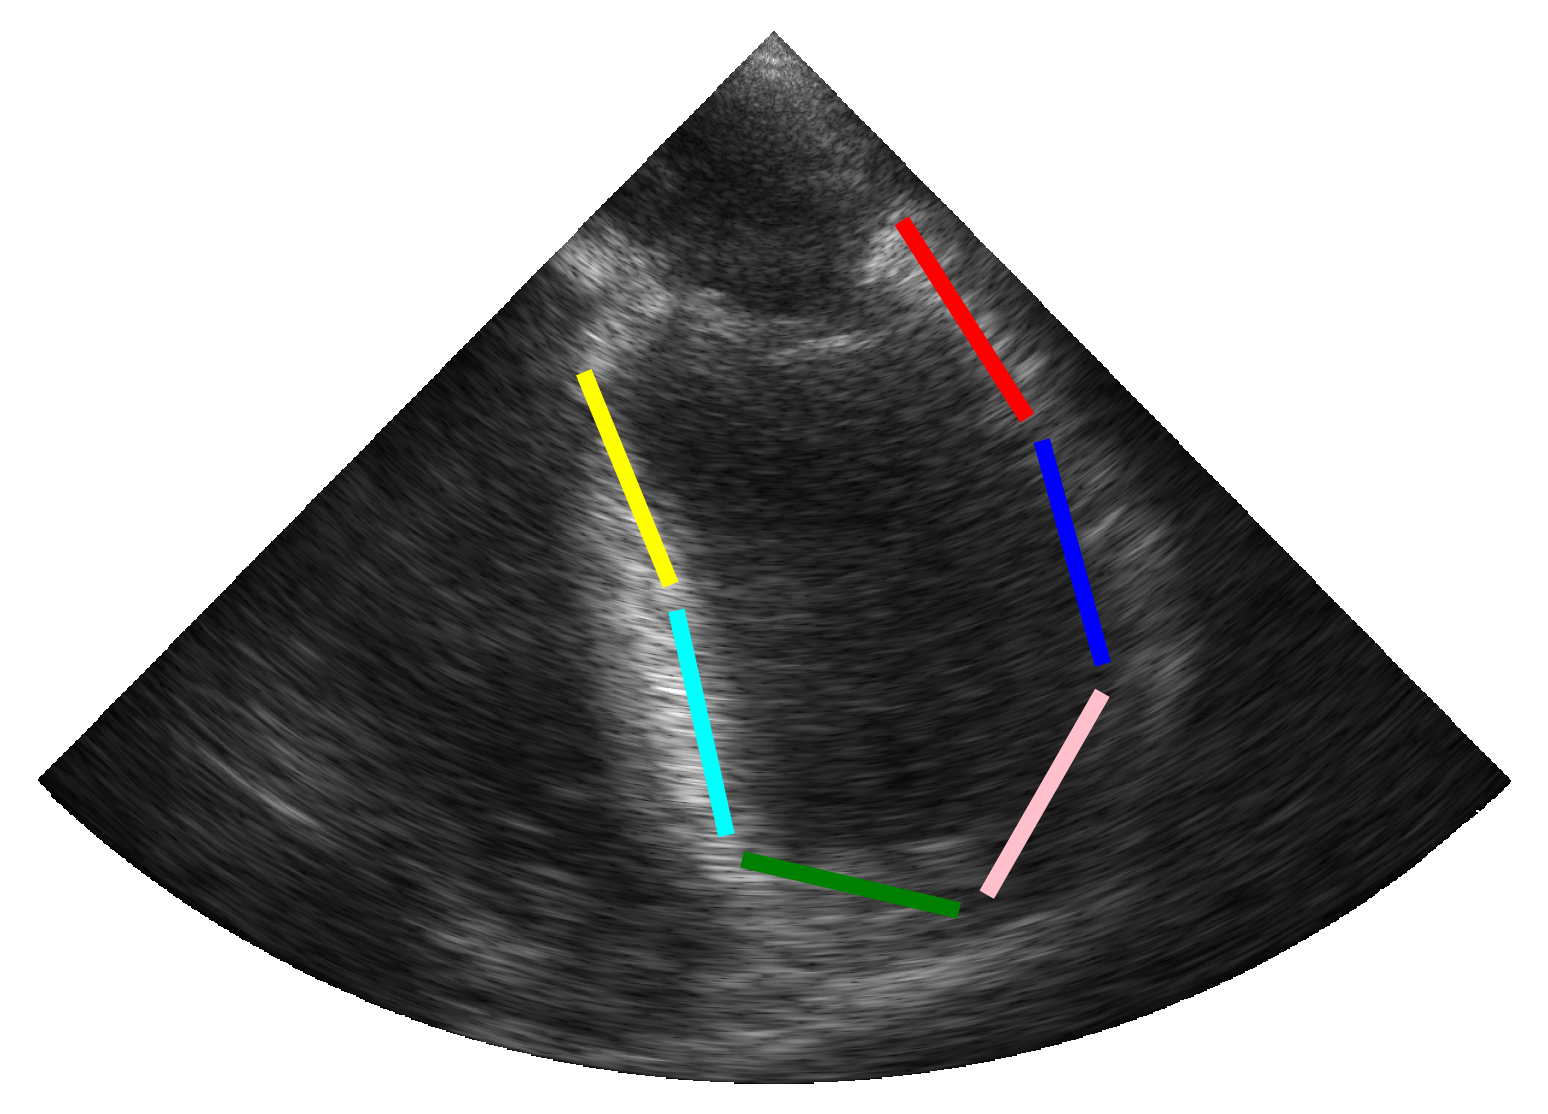

(a)

(b)

(c)

(d)

2.3.2 Simulation of Synthetic Infarction

To account for patients with hypokinetic pathologies, we enhanced the simulation pipeline by designing additional scenarios that simulate myocardial infarction in one of the six cardiac segments. Based on the pipeline described above (c.f. Figure 1), a synthetic myocardial motion was first estimated from a real sequence using the same technique as previously described [14]. The longitudinal contraction of myocardial scatterers was then reduced locally (i.e. at the center of a specific segment) following a Gaussian distribution throughout the cardiac cycle. The scatterers in the surrounding tissues were finally designed to compensate for the reduced contractility in order to maintain overall contraction, thus enabling the rest of the pipeline to be preserved.